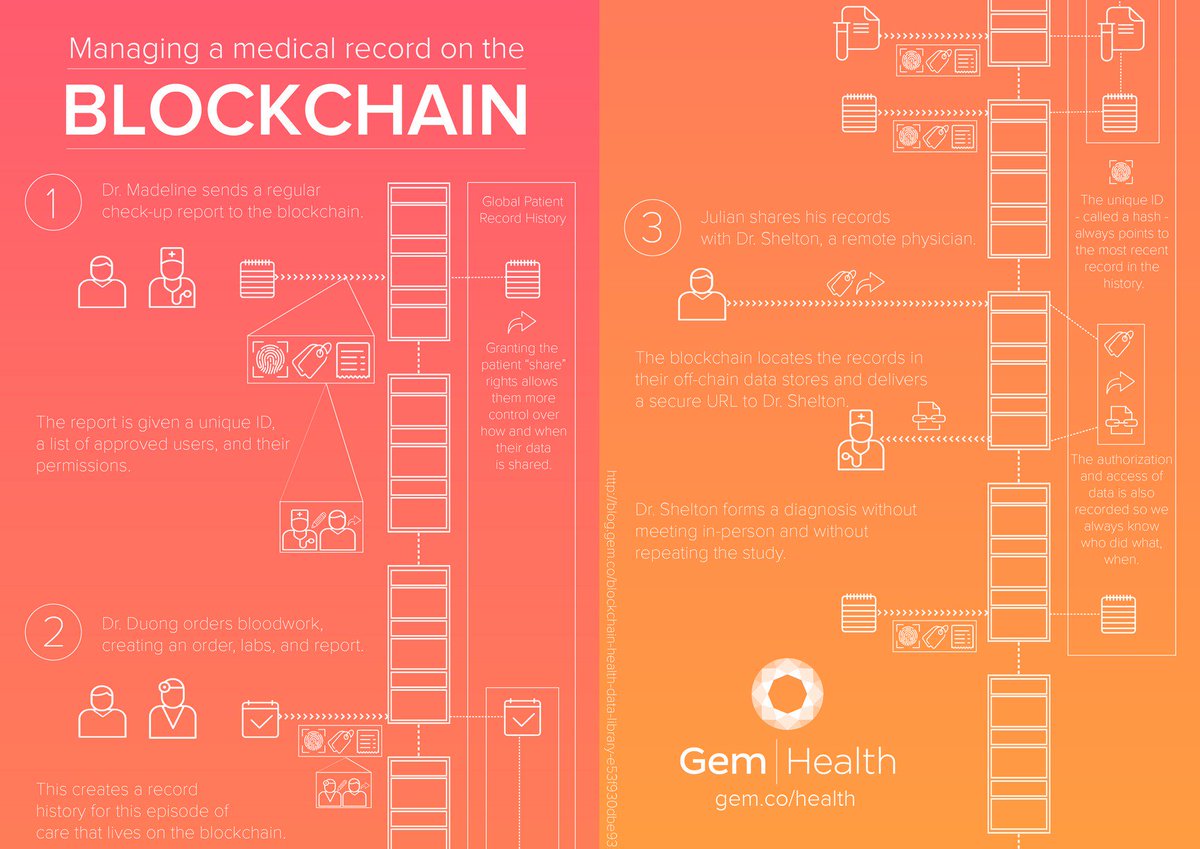

Managing Medical Data on The

#Blockchain [Infographic] https://goo.gl/TvWiWh [by@gemhq]#BigData#HealthTech@ahier@DeepLearn007pic.twitter.com/J3egj0nupv ಧನ್ಯವಾದಗಳು. Twitter ಇದನ್ನು ನಿಮ್ಮ ಕಾಲರೇಖೆಯನ್ನು ಉತ್ತಮಗೊಳಿಸಲು ಬಳಸುತ್ತದೆ. ರದ್ದುಗೊಳಿಸು